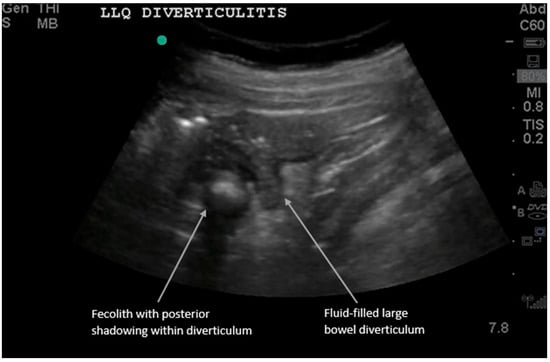

Figure 2.

Acute diverticulitis results from inflammation of a colonic diverticulum and most commonly presents with left lower quadrant pain since it typically involves the descending or distal sigmoid colon. The sonographic diagnosis of diverticulitis, as detailed in recent comprehensive reviews, relies on visualizing diverticula as small outpouchings from the colon wall with posterior acoustic shadowing if gas or feces are present [2,5,13,14,15,16]. We present a long-axis view of large bowel diverticulitis, which has the following characteristics on ultrasound: (i) thickened large bowel wall > 5 mm, (ii) hyperemic bowel wall with color Doppler flow mode, (iii) fluid-filled contents in the diverticula, and (iv) non-compressible hyperechoic fat around the bowel. (See Supplementary Video S1 for examples of dynamic findings.) Sometimes the diverticulum can be visualized with a fecolith, and when this obstructs the diverticular neck, it can develop into diverticulitis. Most cases are uncomplicated (85%) and improve with nonoperative antibiotic treatment. However, complicated cases can show adjacent abscesses, fistulas, obstructions, or free air [6,11,12,13,14,15,16,17].